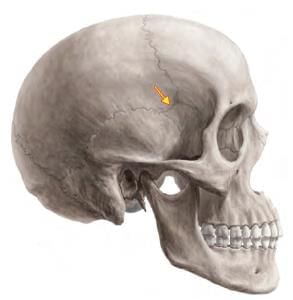

A fracture at the marked arrow (pterion) leads to bleeding of which artery? (AIIMS June 2020)

Detailed Solution for Test: Anatomy - 3 - Question 12

The highlighted area is the pterion, beneath which lies the anterior division of the middle meningeal artery, which may bleed if a fracture occurs at this location. The pterion marks the junction of four bones: the frontal, parietal, and temporal bones, along with the greater wing of the sphenoid bone. The central point of the pterion is referred to as the Sylvian point, where the cranium is notably thin.

• Its immediate deep relationships include the frontal (anterior) branch of the middle meningeal artery, its accompanying vein, and the stem of the lateral (Sylvian) sulcus of the cerebrum.

• The lateral sulcus extends posteroinferiorly from the Sylvian point, situated near the region of the pterion.

A fracture in this area can damage the middle meningeal artery, potentially leading to extradural haemorrhage. The pterion is crucial for the precise placement of burr holes for evacuating extradural haematomas. In neurosurgery, the pterional craniotomy is a frequently used technique to access the middle cranial fossa. Additionally, the pterion is the location of the anterolateral fontanelle, which closes at around six months after birth.

Which structure is deeply related to the arrow marked area? (INI-CET Nov 2020)

Detailed Solution for Test: Anatomy - 3 - Question 13

The highlighted area indicates the ‘H’ shaped suture – pterion, which serves as a significant anatomical reference.

• Surgeons utilise this approach for planning anterior clinoidectomy.

• As the anterior clinoid process forms part of the lesser wing of the sphenoid, it justifies the procedure.

Note: The anterior (frontal) branch of the middle meningeal artery is situated deep to the pterion.

• This artery is susceptible to bleeding in the event of a skull fracture, which can result in a life-threatening extra-dural haematoma.

The anterior clinoid process (ACP) represents the apex of the lesser wing of the sphenoid bone.

• Its anatomical positioning is crucial due to its proximity to surrounding structures such as the optic nerves, internal carotid artery (ICA), and other neurovascular components.

Anterior clinoidectomy (AC) is a vital technique that plays a key role in accessing lesions located at the central skull base, for instance, during the clipping of aneurysms in the para-clinoid region.